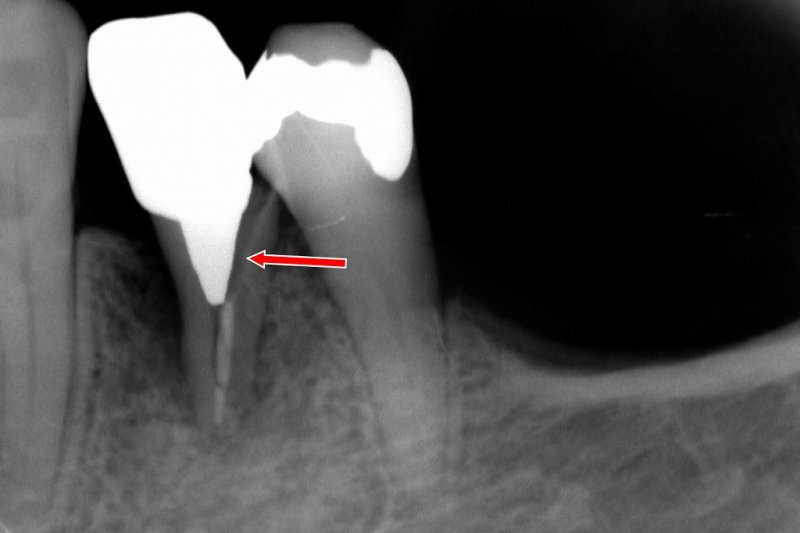

当院は、日本口腔インプラント学会の専門医・指導医が在籍する信頼の歯科医院です。難症例や多数歯のインプラント治療において豊富な実績があり、他院で断られたケースにも対応しています。

特に、サイナスリフトや骨造成といった高度な治療技術を駆使し、患者様一人ひとりの状況に最適な治療法をご提供します。専門的な知識と技術で、複雑な症例にも安心してお任せいただけます。